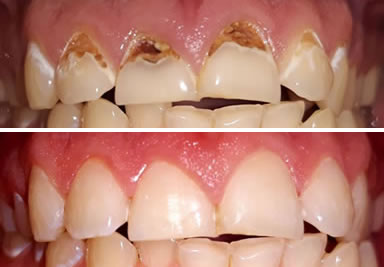

Caries front teeth

multiple lesions in different stages of evolution affecting all frontal teeth

Porcelain crowns and veneers

full porcelain crowns and veneers